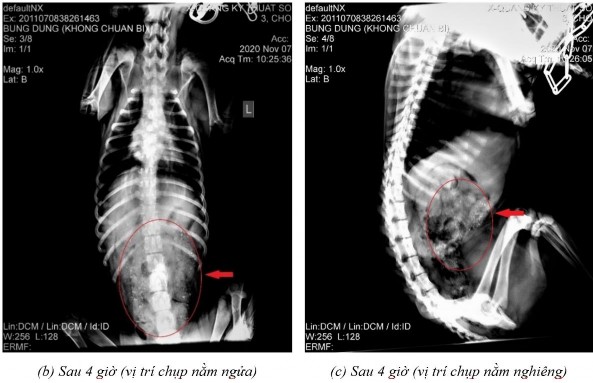

Phụ lục 5.4. Hình ảnh X-quang chó 5 ở thời điểm (a) sau 2 giờ 20 ở vị trí nằm nghiêng, (b) sau 4 giờ ở vị trí nằm ngửa, (c) sau 4 giờ ở vị trí nằm nghiêng, (d) sau 7 giờ ở vị trí nằm ngửa, (e) sau 7 giờ ở vị trí nằm nghiêng, (f) sau 9 giờ ở vị trí nằm ngửa, (g) sau 9 giờ ở vị trí nằm nghiêng, (h) sau 11 giờ 40 ở vị trí nằm ngửa và (i) sau 11 giờ 40 ở vị trí nằm nghiêng